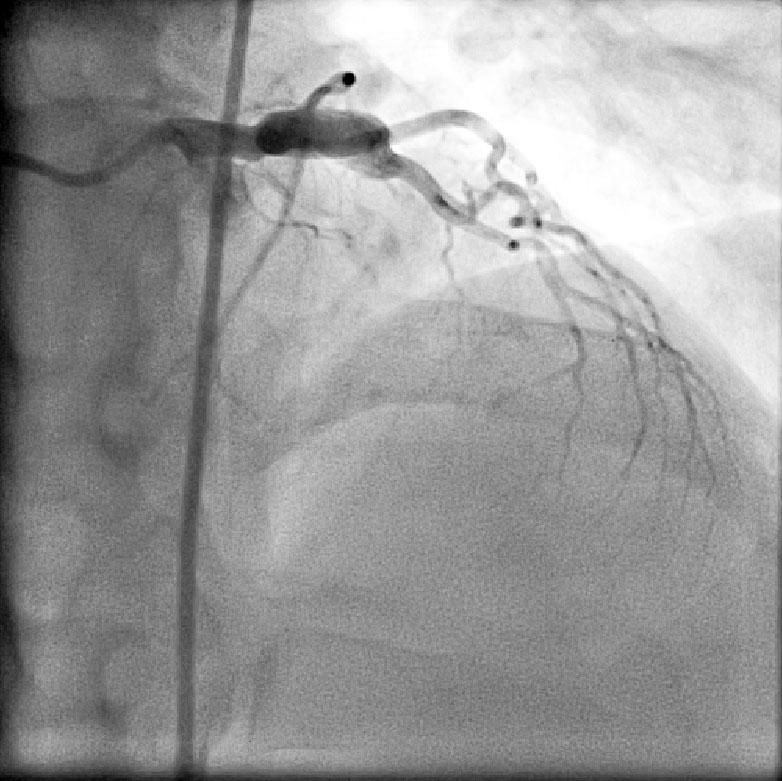

CABG in Kawasakis with Coronary Aneurysms

Angiogram prior to Primary PTCA